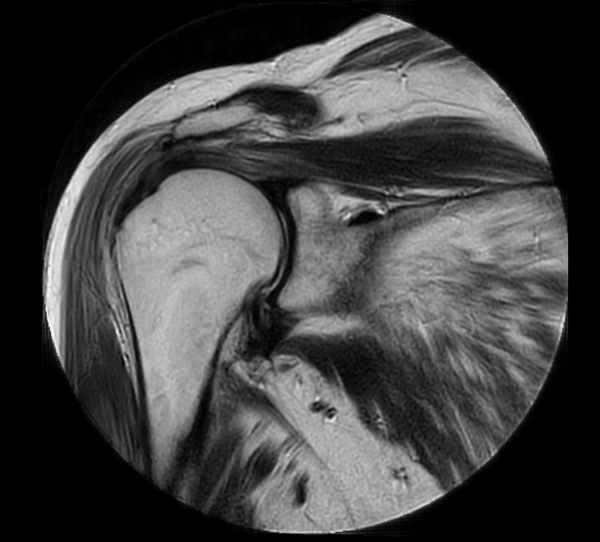

Coronal MultiVane XD - T2w TSE